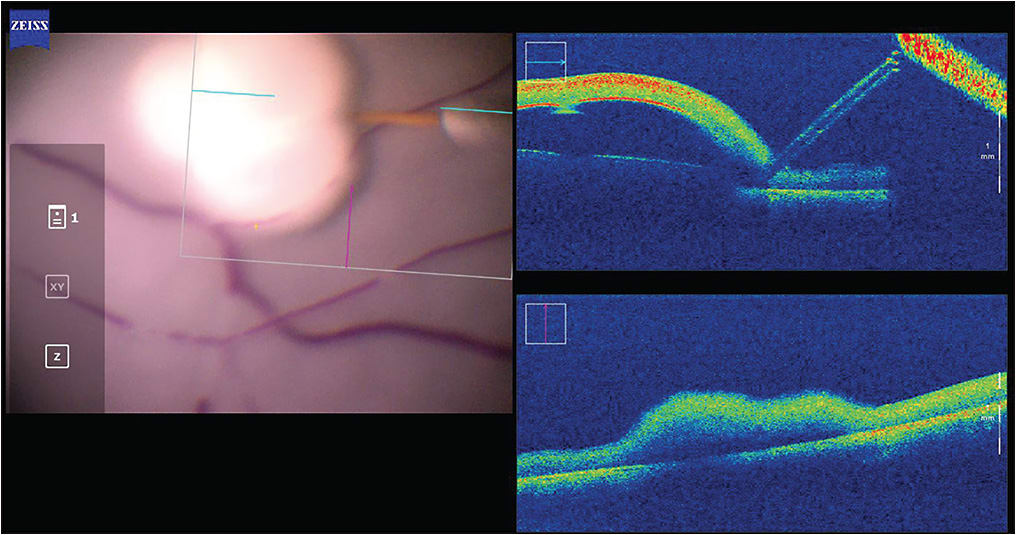

In terms of autonomous robotic systems, all reported studies exist at the research stage without any reported clinical trials. Perhaps the most advanced autonomous intraocular system is the IRISS from UCLA, primarily developed for cataract surgery.7 However, the IRISS has also been used to perform fully autonomous RVC on silicone eye models.8 Using a combination of OCT data and camera images, the system was shown to be capable of cannulating vein phantoms as small as 120 µm without input from a human operator (Figure 3). Important questions remain regarding the representativeness of the artificial vein model and how well this system could be applied to in vivo RVC, but the study’s success lends confidence to the idea that specific steps of surgical procedures can be autonomously performed.